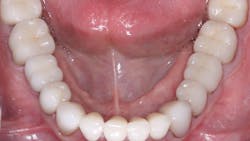

Internal staining of zirconia. Some labs are staining the 3Y, class 5 zirconia in the presintered stage, which improves the color significantly. However, this requires artistic technicians, more time, and a greater cost to the dentist (figure 3).